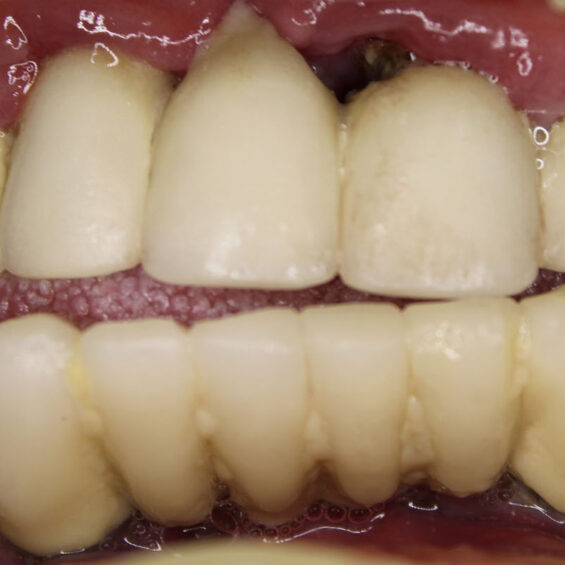

Decidí acudir ya que no aguantaba el dolor que tenía, no podía comer y me afectaba en el día a día. Cuando Susana me exploró, inmediatamente supo lo que necesitaba. Los dientes que me quedaban no podían aguantar más tratamientos Planificó la extracción de todos ellos y el tratamiento de All On Four superior y 6 implantes mandibulares . Con colocación inmediata de dientes el mismo día que me los extrajo y colocó los implantes. Entrar y salir con dientes.

Valentín ha sido en todo momento un paciente comprensivo y colaborador. Su cirugía requirió una planificación muy precisa, pues se trataba de implantes postextracción y carga inmediata. Finalmente, una rehabilitación fija sobre implantes con todos los criterios que exigía.

- Rehabilitación completa sobre implantes